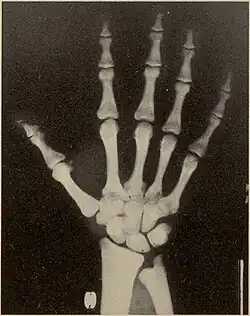

The disease was first described by Maroteaux and Lamy in 1962[4][5] at which time it was defined by the following characteristics: dwarfism; osteopetrosis; partial agenesis of the terminal digits of the hands and feet; cranial anomalies, such as persistence of fontanelles and failure of closure of cranial sutures; frontal and occipital bossing; and hypoplasia of the angle of the mandible.[6] The defective gene responsible for the disease was discovered in 1996.[7] The French painter Henri de Toulouse-Lautrec (1864–1901) is believed to have had the disease.[8]

Pycnodysostosis causes the bones to be abnormally dense; the last bones of the fingers (the distal phalanges) to be unusually short; and delays the normal closure of the connections (sutures) of the skull bones in infancy, so that the "soft spot" (fontanelle) on top of the head remains widely open.[9] Because of the bone denseness, those with the syndrome suffer from fractures.[7]

Other abnormalities involve the head and face, teeth, collar bones, skin, and nails. The front and back of the head are prominent. Within the open sutures of the skull, there may be many small bones (called wormian bones). The midface is less full than usual. The nose is prominent. The jaw can be small. The palate is narrow and grooved. There will be delay in fall of milk teeth. The permanent teeth can also be slow to appear. The permanent teeth are commonly irregular and teeth may be missing (hypodontia). The collar bones are often underdeveloped and malformed. The nails are flat, grooved, and dysplastic. High bone density, acro-osteolysis and obtuse mandibular angle are the characteristic radiological findings of this disorder.[10]

Pycnodysostosis also causes problems that may become evident with time. Aside from the broken bones, the distal phalanges and the collar bone can undergo slow progressive deterioration. Vertebral defects may permit the spine to curve laterally resulting in scoliosis. The dental problems often require orthodontic care and cavities are common.

Pycnodysostosis is one of those disorders which has a typical facial gestalt[15] and can be clinically identified in the majority of cases. Skeletal surveys can also aid in clinical diagnosis and characteristic features include high bone density, acro-osteolysis and obtuse mandibular angle. Molecular testing will be the final resort to confirm the diagnosis. Due to the limited number of exons of the CTSK gene that causes pycnodysostosis, a cheaper genetic testing called Sanger sequencing can be employed to confirm the diagnosis.

Differences from osteopetrosis

Many of the radiological findings of PYCD are similar to those of osteopetrosis, a disease that causes increased bone density due to a defect in bone reabsorption; however, the two diagnoses differ in several ways.[16][17] In PYCD, there is also:[17]

- Hypoplasia or aplasia of the distal phalanges and ribs